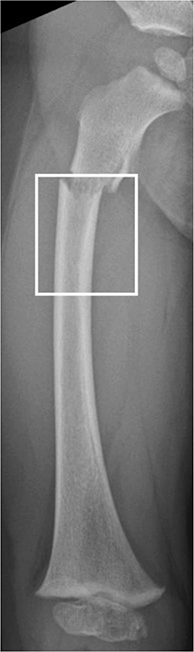

We reviewed radiographs of all proximal femoral fractures and diaphyseal fractures registered in the KIDS Fracture Tool to confirm diagnosis and eligibility. Patients with pathological fractures, slipped capital femoral epiphysis, stress fractures, or avulsion fractures were excluded. Collum and trochanteric fractures were classified using the Delbet classification, which includes transepiphyseal, transcervical, basicervical, and intertrochanteric fractures denoted by Delbet types I–IV, respectively [15]. Subtrochanteric fractures were defined as those occurring entirely within 20% of the total femoral length below the lesser trochanter (Figure 1). Subtrochanteric fractures were classified into complete and incomplete (torus, greenstick) fractures. Patients were followed for a minimum of 1 year and no patient was excluded due to this criterion.

Figure 1. The area located within 20% of the total length of the femur below the lesser trochanter, defines the subtrochanteric fracture area. Subtrochanteric fractures by our definition should be entirely confined to this area, not only extend to it.